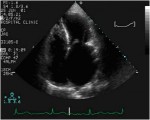

L’ Ecocardiografia rappresenta l’esame diagnostico principale per la diagnosi di insufficienza mitralica. Ci permette infatti la visualizzazione morfologica dell’apparato valvolare e delle camere cardiache, durante tutto il ciclo cardiaco, e quindi ci consente di valutarne lo stato e la funzionalità. Eseguita in prima istanza per via transtoracica (TTE) con la metodica bidimensionale è in grado di chiarire l’etiologia del rigurgito, mentre integrata con le metodiche doppler ci consente di quantificarlo.

Nell’insufficienza mitralica degenerativa l’ecocardiografia deve fornirci una precisa valutazione dello stato e della mobilità dei lembi che vanno analizzati in tutti i loro segmenti tramite le varie proiezioni, in modo da stabilire se vi è allungamento o rottura di corde.

Sebbene le varie proiezioni della TTE ci forniscano molte di queste informazioni, per una migliore definizione anatomica, e per indirizzare il chirurgo verso una chirurgia di tipo riparativo, l’esame viene eseguito anche per via transesofagea (TEE), direttamente in sala operatoria.

Per stabilire l’entità del rigurgito ci si può avvalere di diversi parametri.

L’area del jet di rigurgito, esaminata al color-doppler , è uno dei parametri più usati, soprattutto quando espressa in rapporto all’area dell’atrio sinistro.

ecocardiografia.jpg

Immagine16.jpg

Il diagramma mostra la valutazione della severità dell’insufficienza mitralica usando l’approccio transesofageo con vista asse-lungo. La gravità dell’insufficienza mitralica (1-4+) viene stabilita in base alla lunghezza e alla larghezza del flusso di jet nell’atrio sinistro. LA, atrio sinistro.; RV, ventricolo destro; LV, ventricolo sinistro.